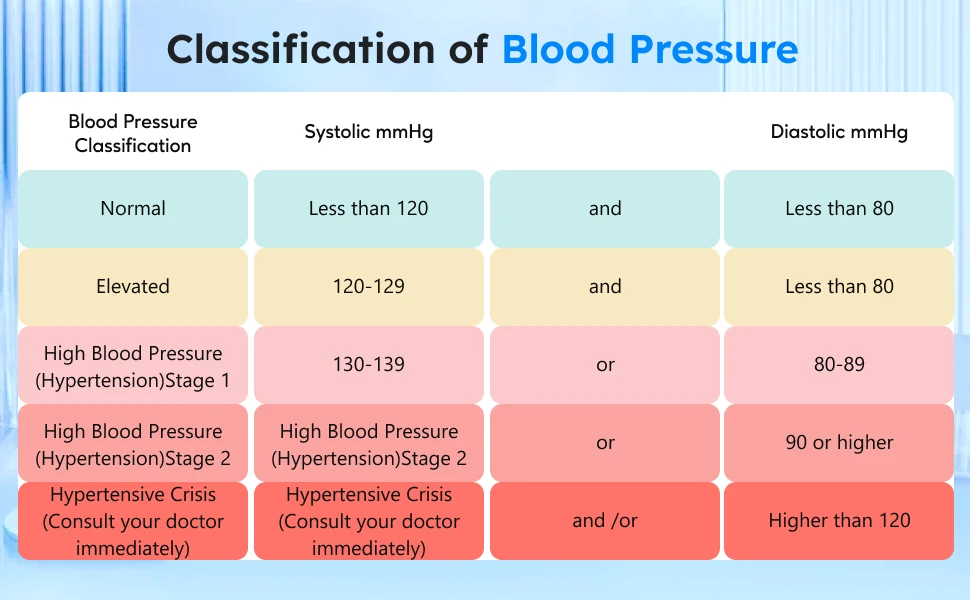

Reasons of monitoring blood pressure everyday:

1. Keep abreast of your own physical condition and avoid unnecessary risks

2. Monitor your body's blood pressure changes, helping doctors getting to know your medical history more accurately and quickly

Features:

1.HD screen display;High quality acrylic lenses

2.Irregular heartbeat detection (IHB function)

3.Blood pressure classification (WHO) indicator

4.2*120 groups memory function

5.Cuff tightness detection (22-42cm cuff)

6.Smart pressure; Overvoltage protection

7.Voice reporting(With English talking voice)

8.Low power prompt

9.Average of last 3 Memories

【Blood Pressure&Heartbeat Indicator】

A coded indicator for blood pressure. The irregular heartbeat symbol will show up when an irregular heartbeat is detected. When a specific error occurs in the product, the cause of the error can be determined by comparing the error symbol with the manual.